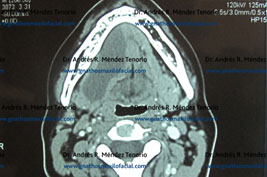

Tomografías computarizadas antes y después del procedimiento quirúrgico

Imágenes de control confirmando la eliminación completa de la lesión